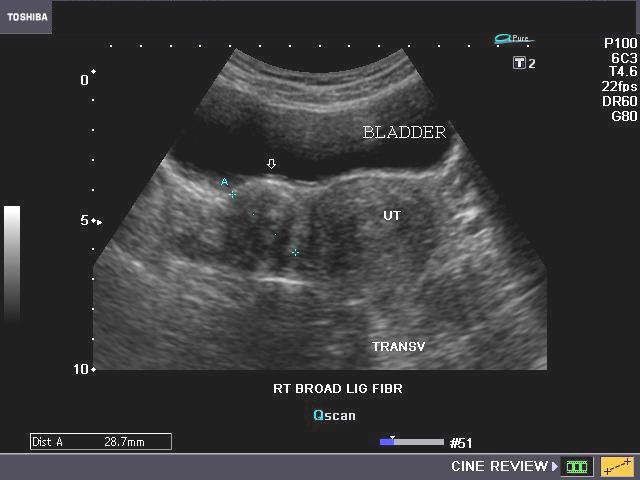

D) Broad ligament fibroid

Interligamentous fibroid or fibroid within broad ligament

Sometimes a fibroid can grow laterally into the region between the two layers of the broad ligament, These ultrasound images show a solid mass to the right of the body of uterus. The mass is non calcific and shows no degenerative changes and appears to occupy the right broad ligament (arrows). This suggests a right broad ligament fibroid (also called interligamentous fibroid). Such fibroids can be difficult to remove surgically due to the vessels passing through the broad ligament.